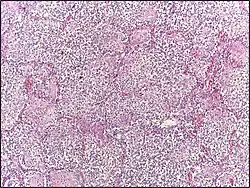

Lobar pneumonia usually has an acute progression. Classically, the disease has four stages:[1]

- Congestion in the first 24 hours: This stage is characterized histologically by vascular engorgement, intra-alveolar fluid, and small numbers of neutrophils, often numerous bacteria. Grossly, the lung is heavy and hyperemic.

- Red hepatization or consolidation: Vascular congestion persists, with extravasation of red blood cells into alveolar spaces, along with increased numbers of neutrophils and fibrin. The filling of air spaces by the exudate leads to a gross appearance of solidification, or consolidation, of the alveolar parenchyma. This appearance has been likened to that of the liver, hence the term "hepatization".

- Grey hepatization: Red blood cells disintegrate, with the persistence of neutrophils and fibrin. The alveoli still appear consolidated, but grossly the color is paler and the cut surface is drier. This is when death typically occurs in severe cases.

- Resolution (complete recovery): The exudate is digested by enzymatic activity, and cleared by macrophages or by cough mechanism. Enzymes produced by neutrophils will liquefy exudates, and this will either be coughed up in sputum or drained via lymph.